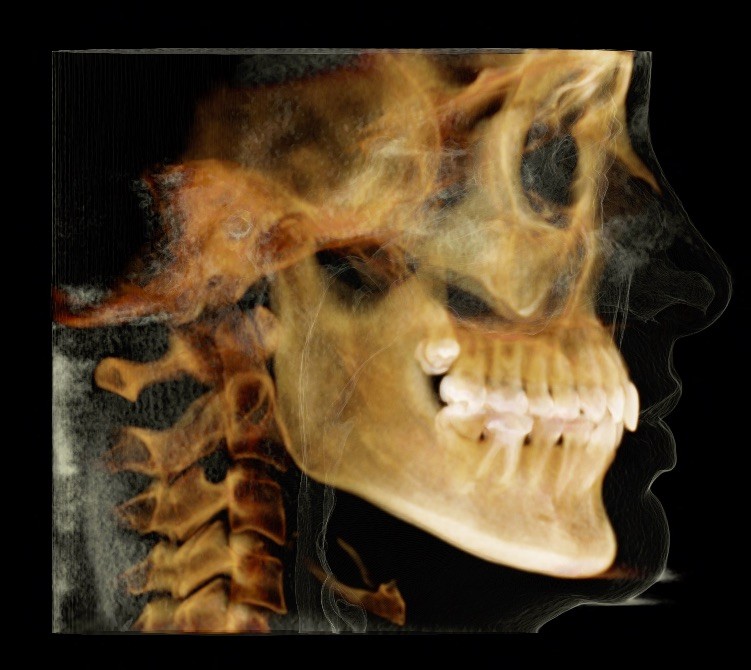

Diagnosis: Lower anterior crowding, LL3 crossbite, deep bite, missing UL6.

X-RAYS